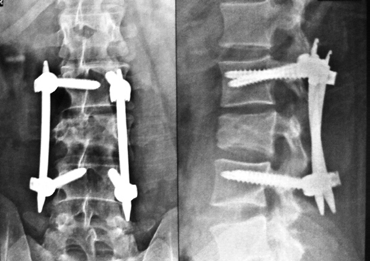

Percutaneous screw fixation and retroperitoneal corpectomy cage reconstruction for fracture spine with only bladder affected.